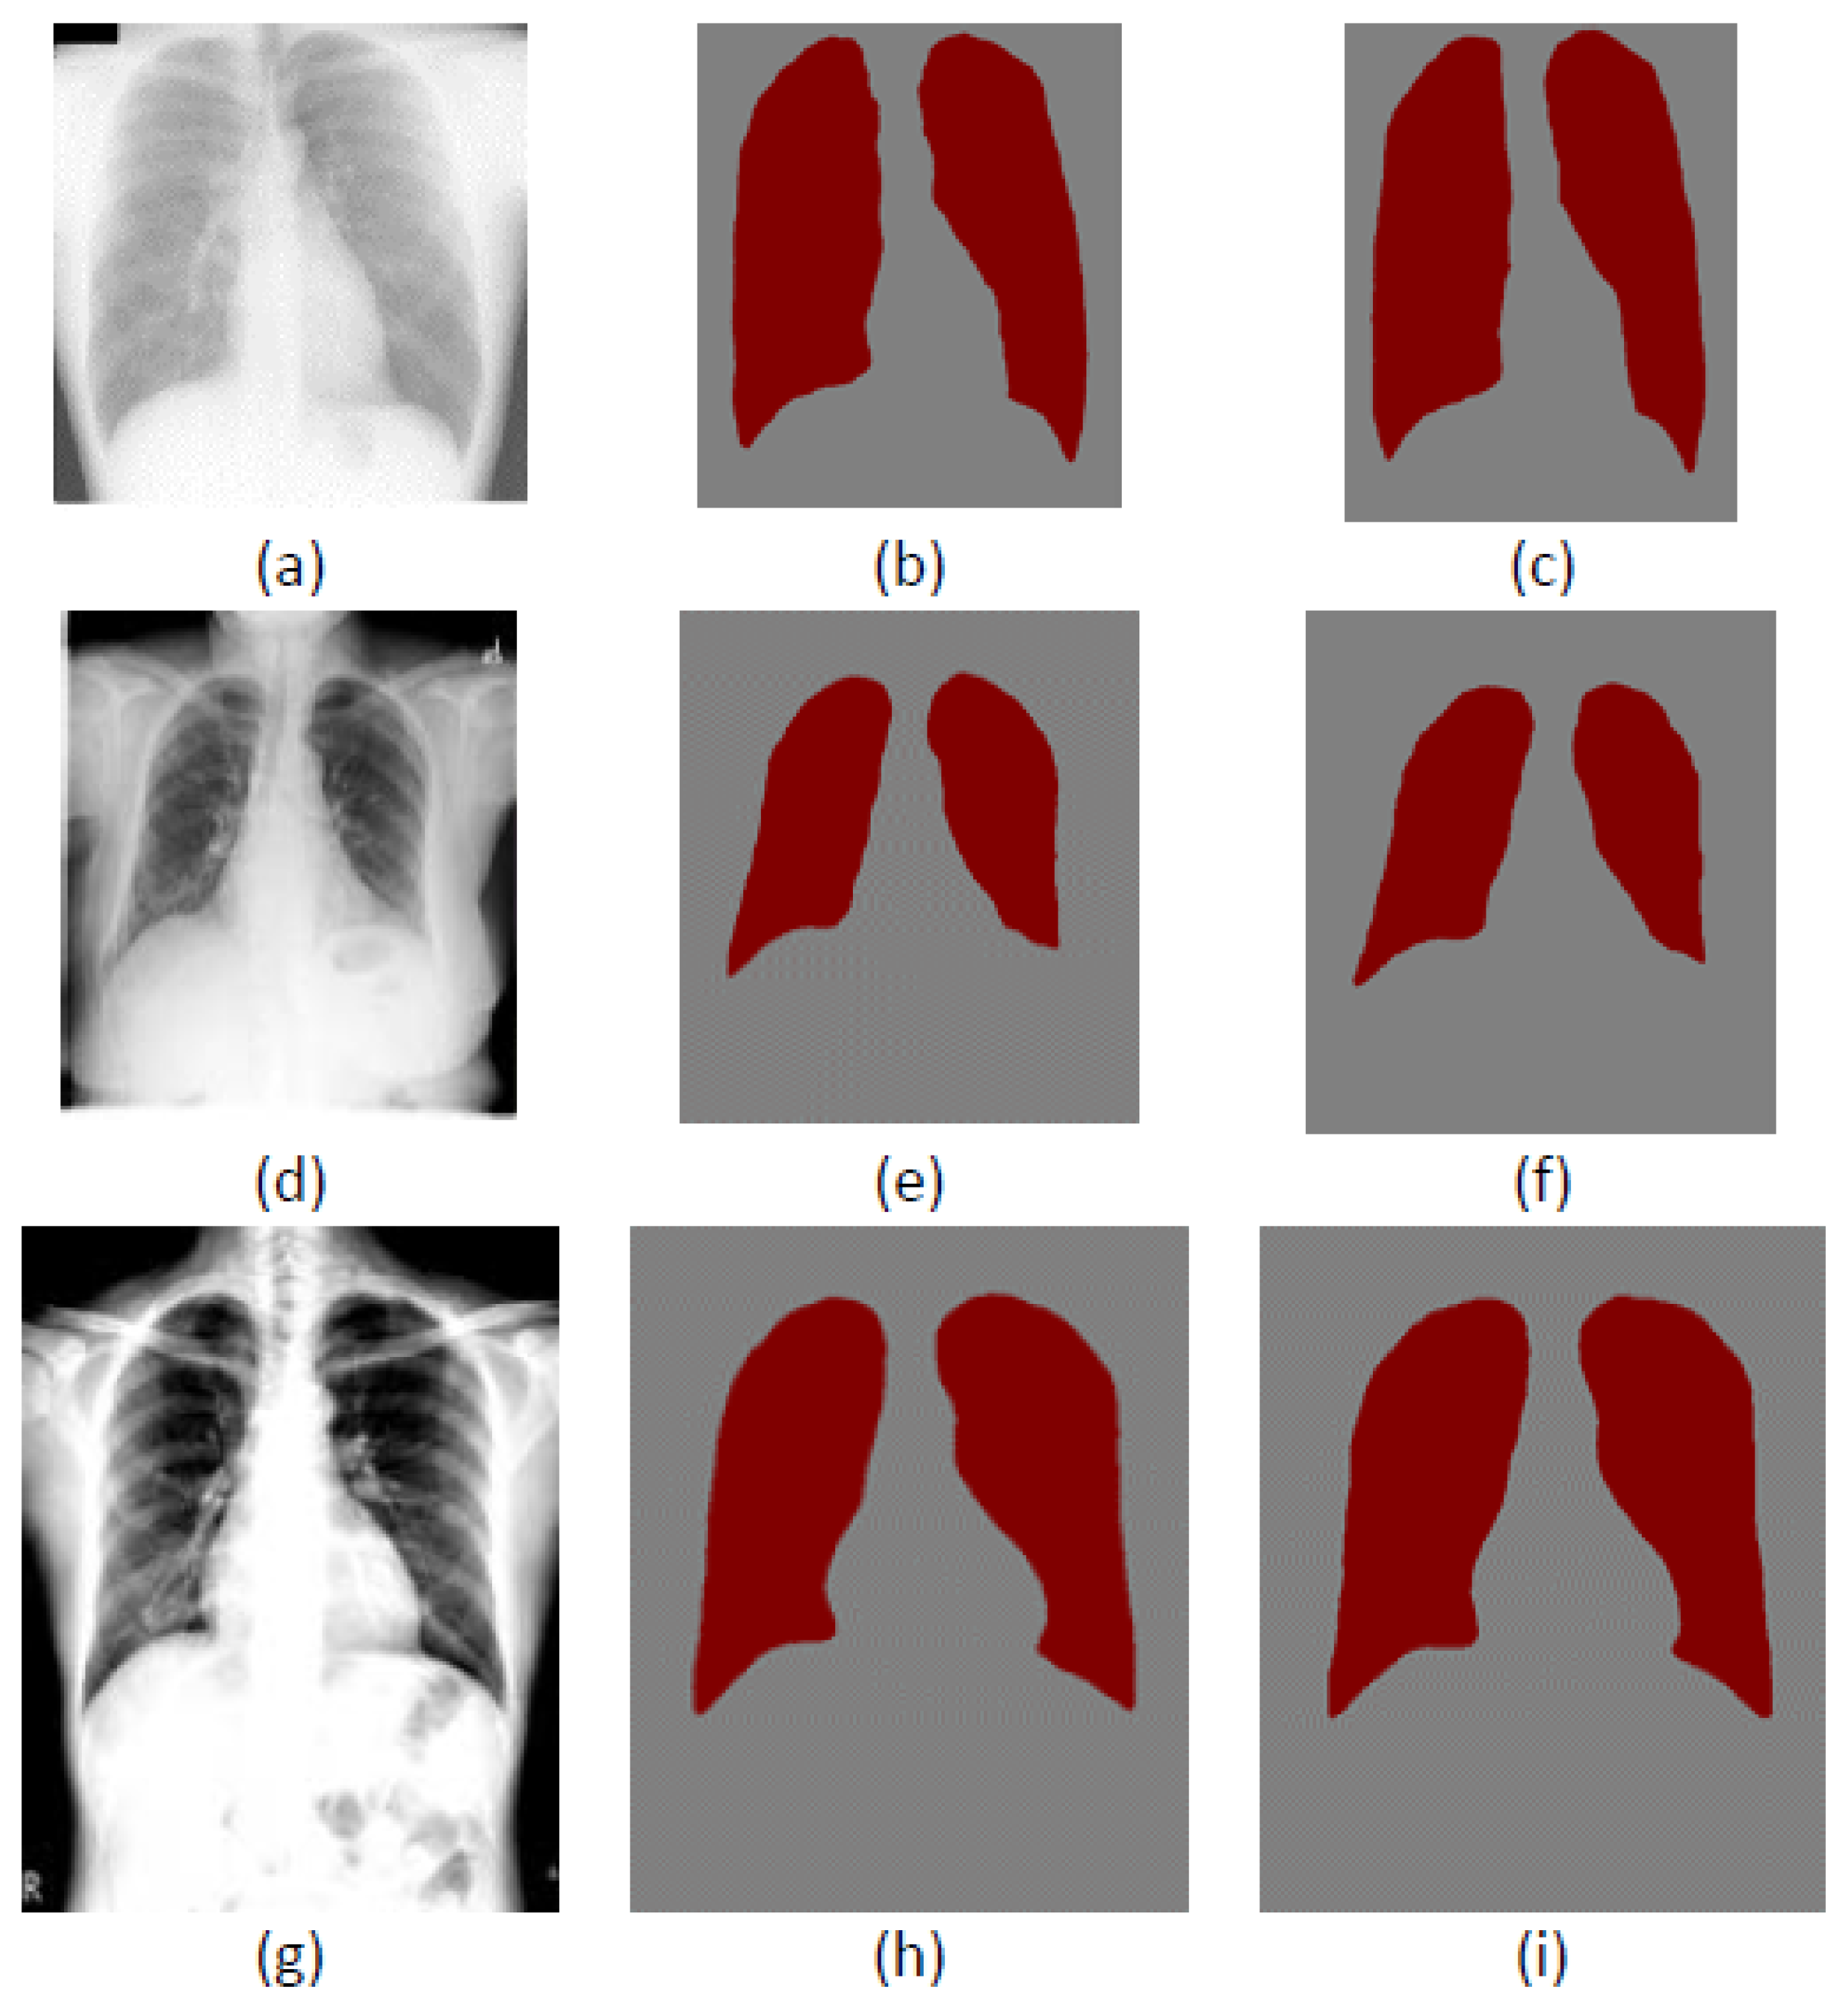

4. Experimental Results

4.3. Cross-Dataset Generalization

4.4. Comparison with other Lung Segmentation Methods